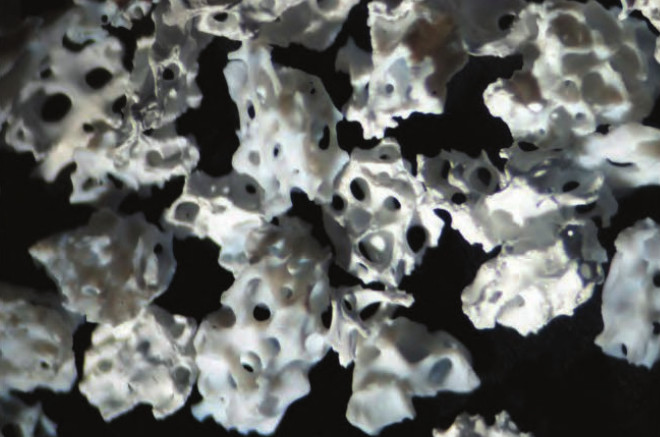

Ti-oss wykorzystuje 100% kości gąbczastej. Większość ksenograftów wykorzystuje mieszankę kości korowej i gąbczastej. Wszystkie ksenografty muszą zostać przetworzone przed użyciem u ludzi w wysokiej temperaturze, tworząc twardsze, gęstsze struktury z mniejszą liczbą mikroporów, które nie są preferowane przez nowe komórki kostne. Ti-oss stosuje wyrafinowaną obróbkę przy użyciu niskich temperatur uzupełnionych o środki chemiczne kontrolujące pH, które zachowują optymalną porowatość i strukturę porów, zapewniając doskonałą zwilżalność, powierzchnię i angiogenezę – prekursor szybkiej waskularyzacji i wczesnego gojenia.

Proces tworzenia nowej tkanki kostnej inicjowany jest poprzez przyleganie skrzepów krwi, co nazywane jest również tworzeniem sieci fibrynowej. Do tego procesu niezbędna jest szorstka i hydrofilowa powierzchnia; bez niej nie można oczekiwać skutecznego wzrostu tkanki kostnej, podobnie jak trudno jest uzyskać tarcie na gładkiej, szklistej powierzchni.

Nasze doświadczenie w produkcji w średnich temperaturach oraz badania prowadzone we współpracy z wiodącymi instytucjami naukowymi pozwalają nam tworzyć materiał przeszczepowy o powierzchni wiernie przypominającej ludzkie kości.